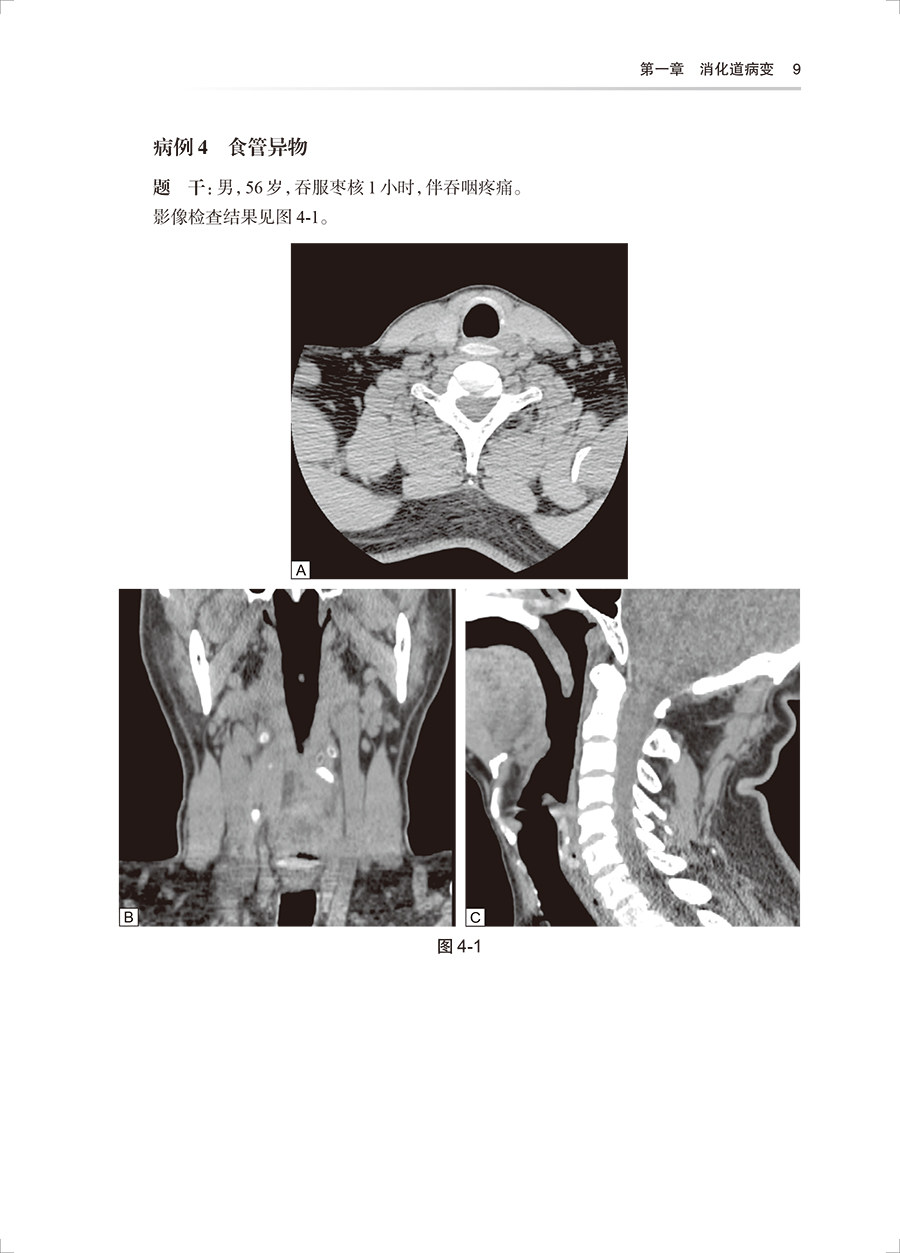

该丛书将由中国医师协会放射科医师分会候任会长梁长虹为第一总主编,中国工程院院士王振常为第二总主编,中华医学会放射学分会前任主任委员金征宇为第三总主编。中国医师协会放射科医师分会常务委员及委员担任分册主编。丛书共分为12个分册,各分册分别对应建立相应的题库(临床阅片实战场景、视频操作和专家视频解读)。内容围绕:放射诊断基本功、放射诊断报告书写、临床思维与决策、实践技能操作和临床医患沟通。其中临床思维与决策是核心问题。 本套书的第4到第10分册依系统分类,根据疾病的发病特点,分列不同的章,不同的章下分列不同的疾病病例。每一病例包括题目(临床资料,影像检查图,问题)、答案、结构化评分表。病例库内容包括病例全套的DICOM图像 + 病例讲解。